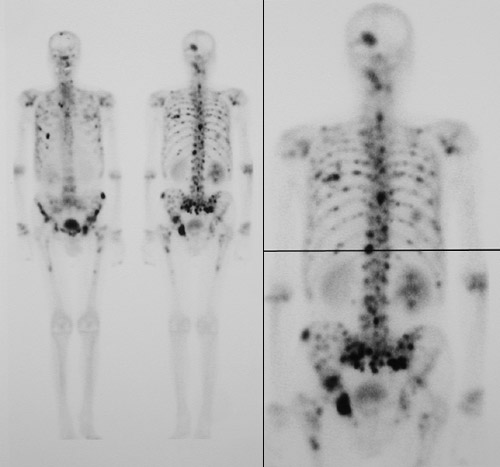

| This nuclear medicine bone scan reveals numerous areas of increased uptake from metastases, which are the darker foci, including the skull. Note the darker right kidney, which is hydronephrotic from obstruction by the primary tumor--a urothelial carcinoma of the bladder involving the right ureteral orifice. |